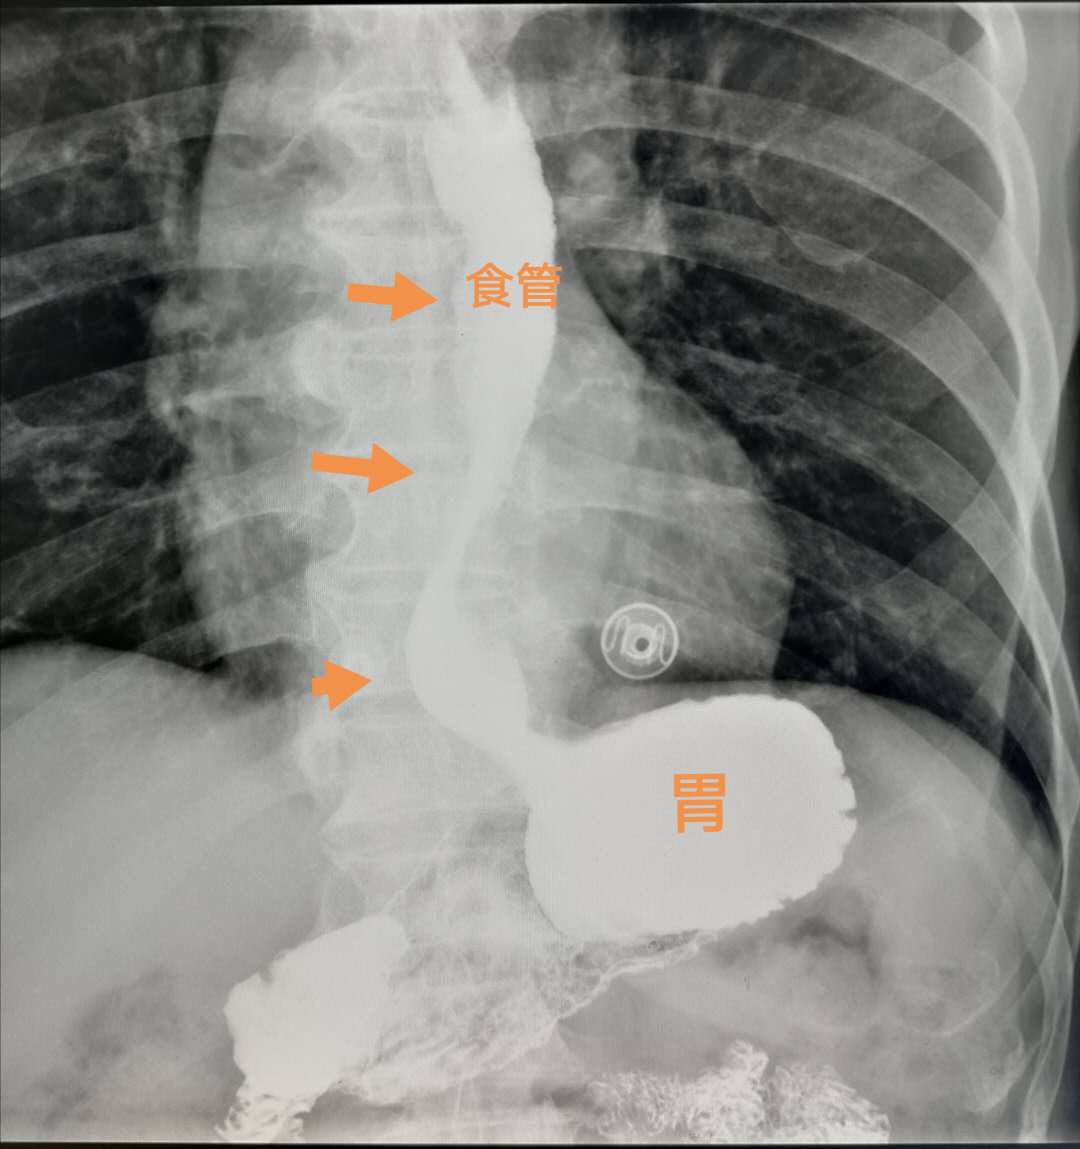

检查结果是胃食管反流。

老人喝下白色的硫酸钡之后,我们卧位观察,可见大量的硫酸钡从胃里反流进入食管,提示她胃上口(贲门)关闭不严。

这种来自胃里的食物反流因为含有胃酸,会反复腐蚀食管,引起胸闷、反酸、胸疼症状,有时候夜间发作可以反流到咽喉部甚至进入肺内,引起反复慢性咽炎、咳嗽、哮喘、发低烧等症状。